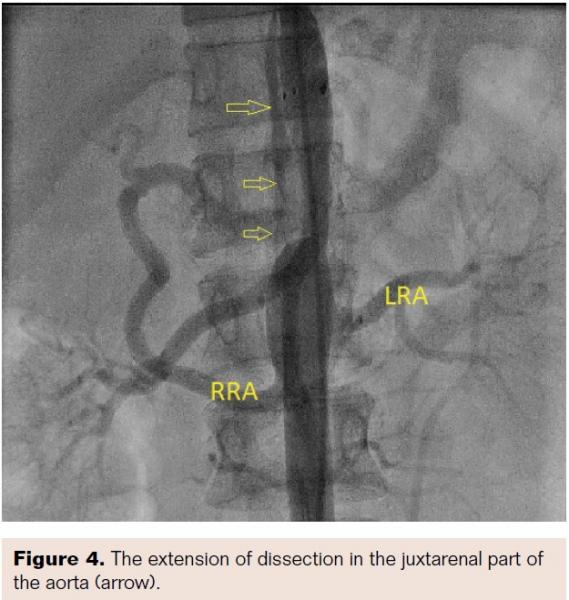

Aortogram confirmed areas of diffuse stenosis and ectasia in the thoracoabdominal aorta, with significant stenosis of the aorta at the level of intervertebral disc between T-11 and T-12 (Figure 2, Video 1). Informed consent for aortoplasty to control secondary hypertension was obtained. Using right femoral arterial access, the occluded segment was crossed using a straight-tip, exchange-length wire (Terumo) and 5 Fr multipurpose diagnostic catheter. The aortic lesion was dilated using an 8 mm x 4 cm Ravel balloon (Bard Peripheral Vascular) at 4 atm; this size was chosen because the narrowest lesion diameter was 5.2 mm (balloon to lesion ratio of 150%). The patient had mild back pain during and after dilation. The pull-back gradient reduced to 50 mm Hg. A dose of 100 mg intravenous tramadol was given. Immediately, a 12 mm x 6 cm E•Luminex self-expanding stent (Bard Peripheral Vascular) was deployed, as we had no covered stent available at the time of intervention. The pull-back gradient reduced further to less than 20 mm Hg. Repeat aortogram by pigtail catheter revealed extensive dissection of the aorta beyond the disease segment (Figures 3 and 4; Videos 2 and 3). No further dilation was attempted. The patient continued to have mild back pain. Beta-blocker was further reinforced by increasing the dose of atenolol to 100 mg twice daily. Her further hospital course was uneventful. At 12-month follow-up exam, the patient continued to be asymptomatic and her hypertension was under control.